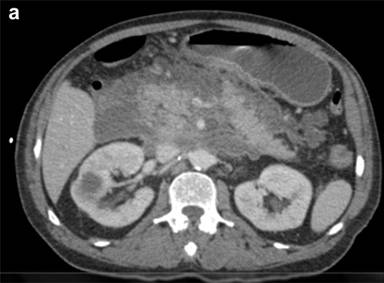

Management

Figure 3. Severe PEP complications of peri-pancreatic necrosis (a.) and pseudocyst (b.) may result in persistent debilitating symptoms and require surgical management for resolution. |